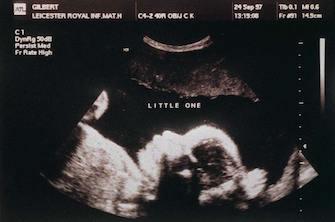

A la naissance, la France compte plus de garçons que de filles. Les scientifiques supposent depuis longtemps que ce déséquilibre existe dès la conception. Une équipe américaine vient de contredire cette idée largement répandue. Le rapport des sexes est équivalent au moment de la conception, expliquent-ils dans la revue de l’Académie américaine des Sciences, PNAS.

Les chercheurs ont analysé les différentes bases de données américaines disponibles sur la conception et la grossesse : fécondations in vitro pour établir le ratio de sexes à la conception, avortements induits, prélèvements des villosités chorioniques, amniocentèses, registres des décès fœtaux et accouchements normaux.

Lors de la conception, on dénombre autant d’embryons de sexe masculin que de sexe féminin. En revanche, les embryons "anormaux" sont plus souvent des garçons. « Le rapport des sexes parmi les embryons anormaux est biaisé en faveur des mâles, le rapport parmi les embryons normaux en faveur des femelles. Ces biais sont associés au statut normal/anormal des chromosomes sexuels et des chromosomes 15 et 17 », écrit l’équipe du Dr Steven Orzack, principal auteur de l’étude. Cela entraîne une surmortalité masculine au cours des deux premières semaines.

A partir de 10 semaines, en revanche, la mortalité féminine domine largement. Ce n’est « pas causé par des anomalies caryotypiques (anomalies des chromosomes, ndlr) telles que des monosomies ou des trisomies, car elles auraient probablement entraîné un décès plus précoce », soulignent les auteurs de l’étude.

Parmi les mécanismes possibles de ce déséquilibre figurent des retards dans le développement des chromosomes X paternels. Ce n’est qu’entre 28 et 35 semaines que la surmortalité féminine s’estompe. « Ce sont des aperçus fondamentaux sur le développement humain précoce », concluent les chercheurs.